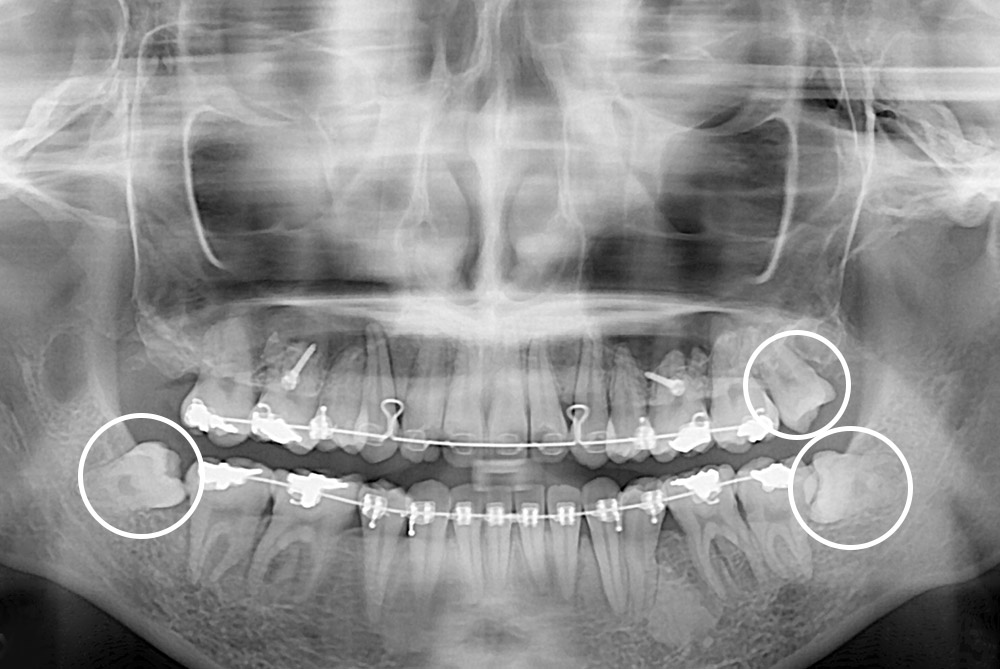

[사랑니] 매복 사랑니 발치

치료후 : 2019-01-31

세종치과는 구강악안면외과학 박사이신 원장님이 발치하는 치과입니다.